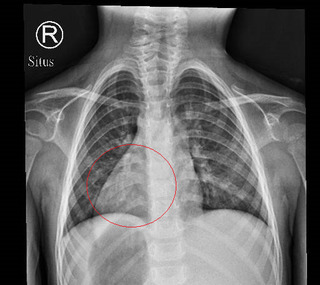

8月身體發熱胸腹水感染,9月開始無法站立,11月初心肝指標異常,連凝血功能都出問題,幸運的是,在11月底等到移植者出現,TANK呂建忠手術主刀醫師王偉林說:「傳統單一的移植都無法解決根本問題,最後一致決定,唯有透過心臟加肝臟的聯合移植手術。」

記者會上主刀醫師,也出面親自說明,TANK的手術,是在浙江大學醫學院附屬第二醫院進行過去曾有浙江二院的醫師,分享一年內操刀大量移植手術,移植的器官來源遭到質疑,而這次TANK也在這動手術,難免引發外界聯想。